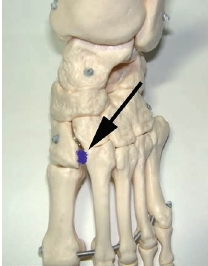

Mittelfußverletzungen im Sport, insbesondere Kapselbandverletzungen, haben in den letzten Jahren zugenommen 1 2 3. Dabei handelt es sich vor allem um Verletzungen des Lisfranc-Bandkomplexes. Der Lisfranc-Ligamentkomplex umfasst einen dorsalen und einen plantaren Anteil. Die Bandzüge verbinden das Os cuneiforme mediale mit der Metatarsale-II-Basis (Abb. 1). Das Ausmaß der Schädigung variiert stark – von der Zerrung bis hin zur vollständigen Zerreißung mit Diastase zwischen dem ersten und zweiten Metatarsale, ggf. auch mit Schädigung der angrenzenden Gelenkfiächen. Die leichteren und mittelschwer ausgeprägten Verletzungen werden häuflg erst verzögert diagnostiziert 4. Nicht selten sind diese Verletzungen Ursache langanhaltender Beschwerden und Sportunfähigkeit.

Diskussion

Der Lisfranc-Bandkomplex spielt eine zentrale Rolle bei der Stabilisierung des Längsgewölbes 38. Eine weitere Besonderheit ist, dass die Basis des Os metatarsale II die anderen Mittelfußknochen nach proximal überragt. Die intermetatarsalen Bänder verbinden vor allem plantar mit sehr kräftigen Zügen die Ossa metatarsale II bis V 39. Zwischen dem ersten und zweiten Strahl gibt es keine intermetatarsalen Bänder 40. Das LisfrancBand spielt deshalb eine entscheidende Rolle in der Stabilisierung der Lisfranc-Gelenklinie. Es entspringt der lateralen Oberfläche des Os cuneiforme mediale. Der plantare Anteil läuft schräg nach plantar und lateral, um an der Basis des Os metatarsale II zu inserieren. Die dorsalen Anteile des Lisfranc-Bandes ziehen fußrückenseitig vom Os cuneiforme mediale zum Os metatarsale II (siehe Abb. 1). Insgesamt sind Verletzungen des Lisfranc-Bandkomplexes selten. In der Literatur wird über eine Häufigkeit von 1 auf 50.000 Personen berichtet 41. Meist ist diese Verletzung dann die Folge von Hochrasanztraumata wie z. B. Verkehrsunfällen und ist kombiniert mit ausgeprägten Zerreißungen von Kapseln und Bändern in der gesamten Lisfranc’schen Gelenklinie 42.